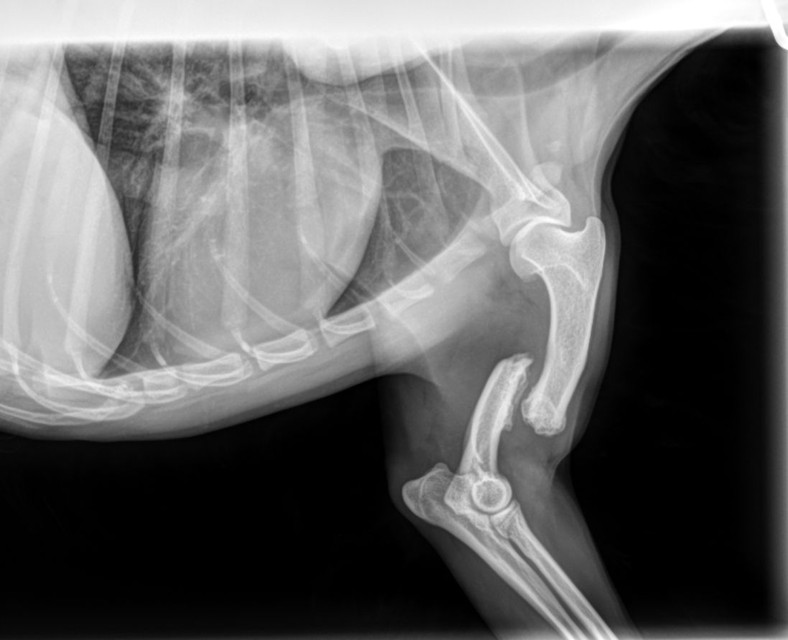

Unser kleiner Yoko, ein junger Yorki- Mischling (geb. 2024), hat sich beim Spielen mit seinen Hundefreunden schwer verletzt. Am vergangenen Mittwoch brach er sich beim Toben im Auslauf überraschend den linken Vorderlauf – ein schmerzhafter und dramatischer Moment für alle Beteiligten.

Unsere Kollegin eilte sofort zu ihm und umgehend brachten wir ihn hier zum Tierarzt. Dort stellten die Ärzte nach dem Röntgen einen Bruch von Radius und Ulna fest. Die Verletzung war so schwer, dass eine spezialisierte Operation in einer Tierklinik nötig wurde.

Bereits am Freitagmorgen fuhr Yoko in die Klinik – und am Nachmittag konnten wir ihn zum Glück wieder in die Arme schließen. Die Operation war erfolgreich: Eine Osteosynthese mit einer 2mm Knochenplatte war notwendig.

Doch damit ist es nicht getan – in der nächsten Zeit benötigt er Schmerzmittel, strikte Leinenruhe, Physiotherapie und einige Zeit später eine zweite OP, um die Platte wieder zu entfernen.